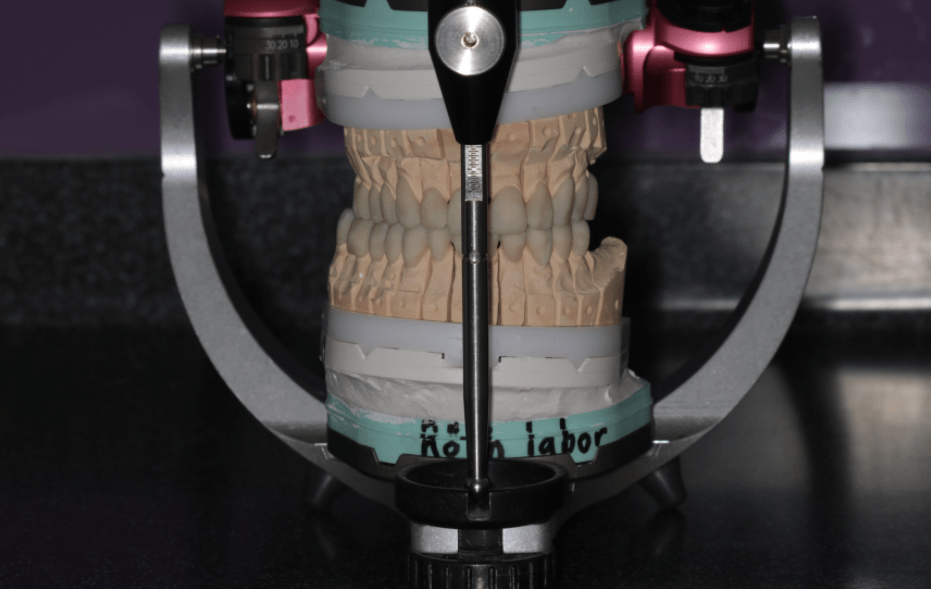

Szükség lehet speciális gyógytornára, egyénre szabott éjszakai sín hordására, akár megfelelő fogszabályozó készülék, illetve fogpótlás elkészítésére is. Ilyen esetekben speciális bemérésre van szükség, amihez úgynevezett nyílhegyrajzoló készüléket, arcívet, pozíciós harapásokat használunk, és segítségül hívhatjuk a legmodernebb, erre a célra létrehozott készüléket: az ARCUSdigmát.

Az állkapocs helyzetének, mozgásának megállapítására, esetleges hibáinak felderítésére az ARCUSdigma rendszer szolgál. A KaVo ARCUSdigma egy elektronikus regisztrációs rendszer, amely 3 dimenziós, ultrahangos méréseken alapul, a páciens egyéni alsóállkapocs-mozgásait méri a koponyához viszonyítva, minden olyan beállítási értéket kiszámít a fogtechnikusok számára, amelyek az artikulátor programozásához és az egyedi, funkcionális fogpótlások készítéséhez szükségesek.

Majd ezt követően arcívvel meghatároztam a felső állcsont koponyához való elhelyezkedését, intraorális rajzolóeszközzel a felső és az alsó állcsont egymáshoz való viszonyát, majd az Arcus Digma készülékkel az individuális mozgáspályákat. Ez mind szükséges ahhoz, hogy egyedi, az egyén számára legkényelmesebb fogpótlás elkészülhessen, melytől jelen esetben páciensünk panaszainak rendeződését vártam.

Ezek segítségével a fogtechnikai laboratórium elkészített egy hosszú távú, ideiglenes pótlást, amelyet a páciens 3 hónapon át hordott, természetesen szoros nyomon követés, kontrollok mellett. Ennyi idő alatt a páciens panaszai nagyrészt meg is oldódtak.